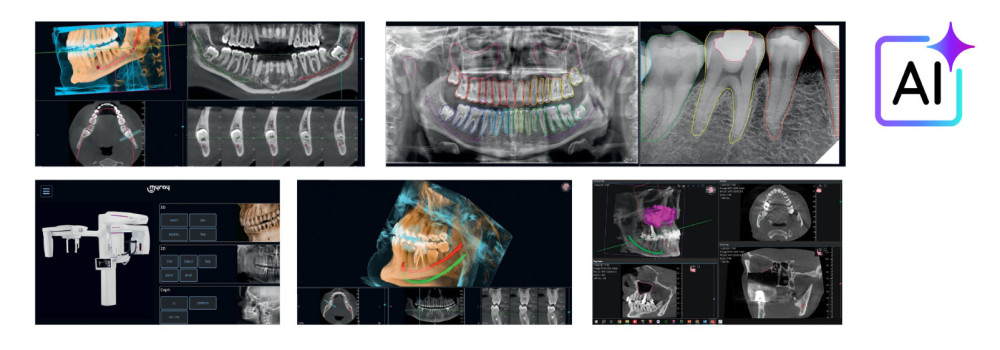

Skaitmenizacija odontologijoje taip pat ženkliai pagerino diagnostikos tikslumą. Kiekviena diagnozė tampa tikslesnė pasitelkus skaitmenines 2D ir 3D technologijas. Pažangūs įrankiai, filtrai, dirbtinio intelekto integracija, programinė įranga ir skaitmeninio apdorojimo sistemos leidžia išgauti itin detalius duomenis, padedančius tiksliau nustatyti burnos ertmės patologijas ir daugeliu atvejų net užkirsti kelią jų vystymuisi. Galimybė vizualizuoti tai, ko plika akimi nematyti, tapo vienu svarbiausių veiksnių užtikrinant geresnius klinikinius rezultatus, o pastaraisiais metais skaitmeninės technologijos odontologijoje šį aspektą dar labiau sustiprino.

Foto: skaitmenizacija odontologijoje – galimybė matyti tai, ko plika akimi nematyti